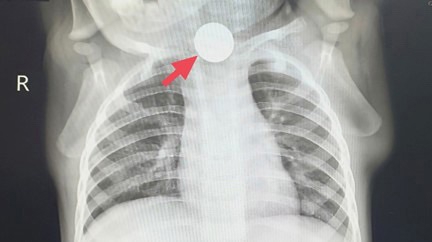

“稳妥起见,先去拍个胸片,排除肺部问题!”门诊医生叮嘱家长,心里却始终悬着一块石头。没想到,这份胸片报告带来的不是安心,而是惊天发现:冬冬食道上段,赫然卡着一枚硬币!

瞬间真相大白:所谓的“厌食”,是硬币卡喉导致吞咽疼痛,孩子根本不敢进食;频繁流口水是因为吞咽受阻,口水无法正常下咽;咳嗽则是口水呛入气道引发的反应。此前的“受凉”“胃口差”,全是误导判断的假象!

“孩子食道卡了一枚硬币,已经滞留一周,快准备内镜取物!”接到紧急通知后,内镜中心医护团队迅速就位,做好术前准备。随着胃镜缓缓插入,可见那枚牢牢卡在食道上段的一元硬币,周围黏膜已被磨得红肿发炎,甚至出现了深深的溃疡,正不断渗血。医护人员小心翼翼操作内镜,精准夹取硬币,全程紧张却有序,最终成功将硬币取出。看着取出的硬币,冬冬爸妈又心疼又后怕,紧紧握着医护人员的手连声道谢。